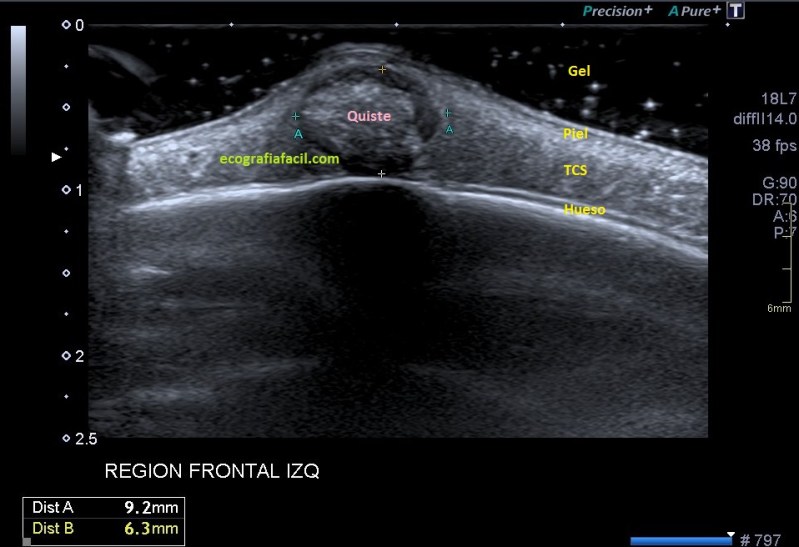

Lo primero que quiero que tengas en cuenta es la localización del bulto, ves que es supersuperficial. Para estudiar este tipo de lesiones lo que debes hacer es tener una buena capa de gel sobre el tumor. Esto se hace con efecto de apoyar la sonda sobre el gel y no sobre la piel para no deformar la lesión, así que es muy importante la técnica y pericia de la operadora que esté ejecutando el estudio.

Lo segundo es localizarlo perfectamente en su ubicación, y ver a qué planos pertenece, si está tocando o no la estructuras que están a su alrededor. En el caso de esta lesión vemos que está en justo debajo de la piel, en el escaso espesor de tejido celular subcutáneo que existe en la región frontal, que es donde la mujer tenía este tumor.

Tercero y último. Ahora lo medimos y lo estudiamos ecográficamente, acotándolo. La semiología es importante, en este caso, el tumor tiene un aspecto hipoecogénico, pero en el centro es hiperecogénico, pero además, dentro de esta hiperecogenicidad existe un grado más de hiperecogenicidad perteneciente a una calcificación grosera. Sus bordes son definidos y con la salvedad de las zonas de calcio, el tumor transmite bien. Su aspecto es heterogéneo, no presenta vascularización, la que ves en la imagen es artefacto de aliasing provocado por el calcio de la lesión.

En estos casos donde el tumor está tan cerca del hueso hay que asegurarse de que éste está indemne. Se demuestra que la lesión no afecta al hueso y que está circunscrita al ámbito puramente subcutáneo.